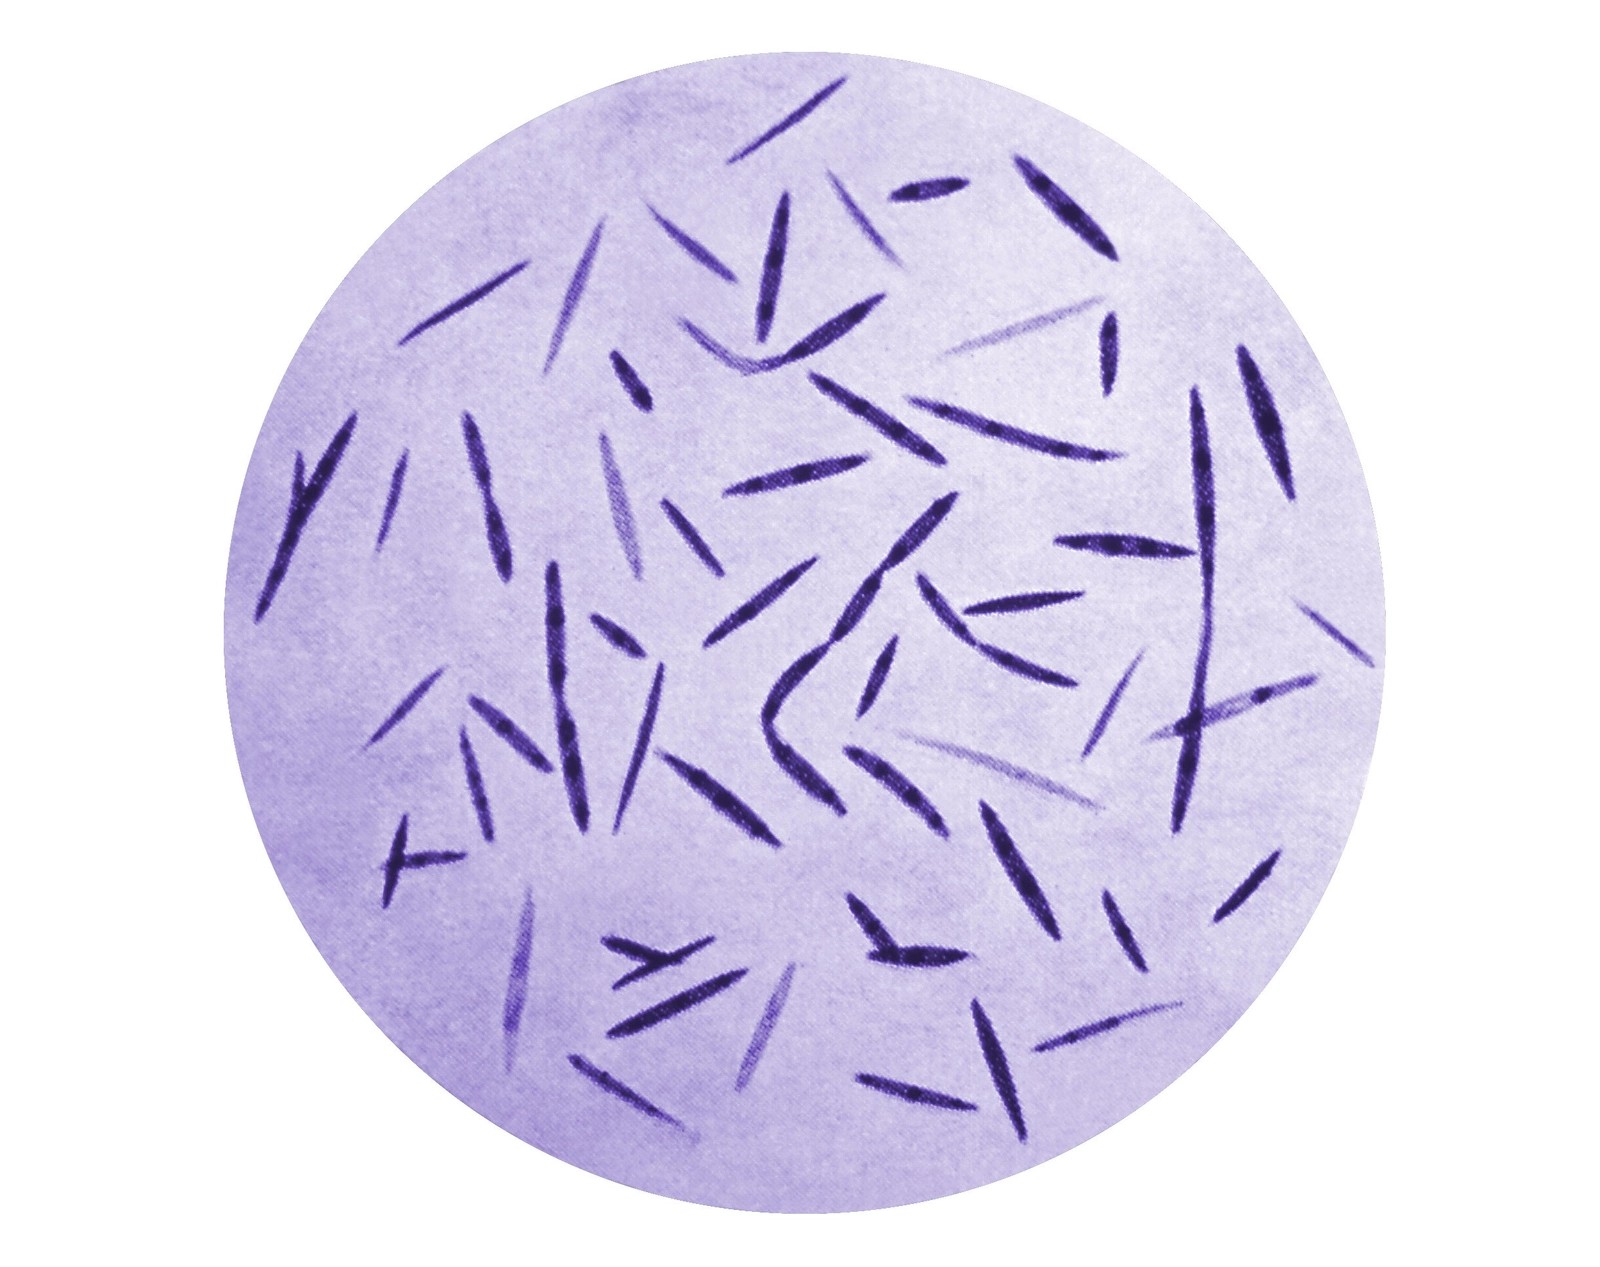

Le 14 juin 2023, une étude japonaise de l’école supérieure de médecine de l’Université de Nagoya, dirigée par le Docteur Ayako Muraoka et le docteur Yutaka Kondo a été publiée dans la revue Science Translational Medicine. Cette étude révèle le rôle d’une bactérie, le Fusobacterium, dans le développement de l’endométriose. Envisagée sous un angle différent, les perspectives curatives sont prometteuses.

Les chercheurs ont découvert qu’une « infection bactérienne au niveau de l’endomètre », était responsable d’une « réponse du système immunitaire ». Il s’agit de la bactérie Fusobacterium. Elle contribue à transformer le fibroblaste en myofibroblaste, induisant la croissance de l’inflammation dans les cellules de l’endomètre, puis dans d’autres zones de la cavité pelvienne, voire abdominale.

La deuxième piste d’explication a été vérifiée en laboratoire. De nombreuses personnes présentent cette bactérie au niveau de la cavité buccale. Il était alors probable que la circulation sanguine entraîne la bactérie jusqu’à l’utérus. « Nous avons alors injecté le fusobacterium dans la veine cervicale d’une souris, près de sa bouche », raconte le Dr. Kondo. « Nous avons constaté que pour la moitié des sujets, le fusobacterium migrait dans l’utérus. C’était incroyable ! ». Le travail de repérage par fluorescence a également permis de confirmer que la bactérie présente dans la majorité des cas était le fusobacterium.

Les résultats de l’étude montrent que 64 % des patientes présentant une endométriose sont testées positives au fusobacterium. « Toutes les endométrioses ne sont pas causées par des infections bactériennes », nuance le Dr. Kondo. Plusieurs facteurs peuvent en être la cause. Le facteur génétique revient souvent. Il peut certes jouer un rôle, tout comme les fluctuations hormonales, ou les conditions environnementales, mais plus de 10 % de la population féminine mondiale en souffre. « Cela représente tellement de personnes que nous ne pouvions pas simplement l’expliquer par une réponse génétique ». « Nous pensons », poursuit le Dr. Kondo « que l’infection au fusobacterium, du fait de sa capacité à se propager, pourrait être l’une des principales origines dans le développement de l’endométriose ».